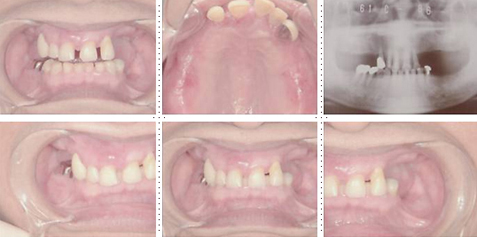

症例10

64才 男性

地元の有名寿司屋さんの店主の方(インプラント患者さん)からの御紹介です。

上顎の義歯をインプラントに変えたいとの希望で来院されました。

このケースはまずはじめに局部床義歯を作り直します。インプラント部と義歯床が接触するのを避ける為、部分的に床を削れるようにクラスプ、補強線の位置を決定します。顎骨の質・量ともに十分で、インプラント埋入は簡単です。右側4本のインプラント埋入は8分で終わりました。3ヶ月後には残存歯全て抜歯し、フルブリッジタイプの仮歯をセット。仮歯の段階で十分に咬合のチェックをし、3~4ヶ月抜歯窩の治癒を待ち最終的にフルブリッジへと移行します。